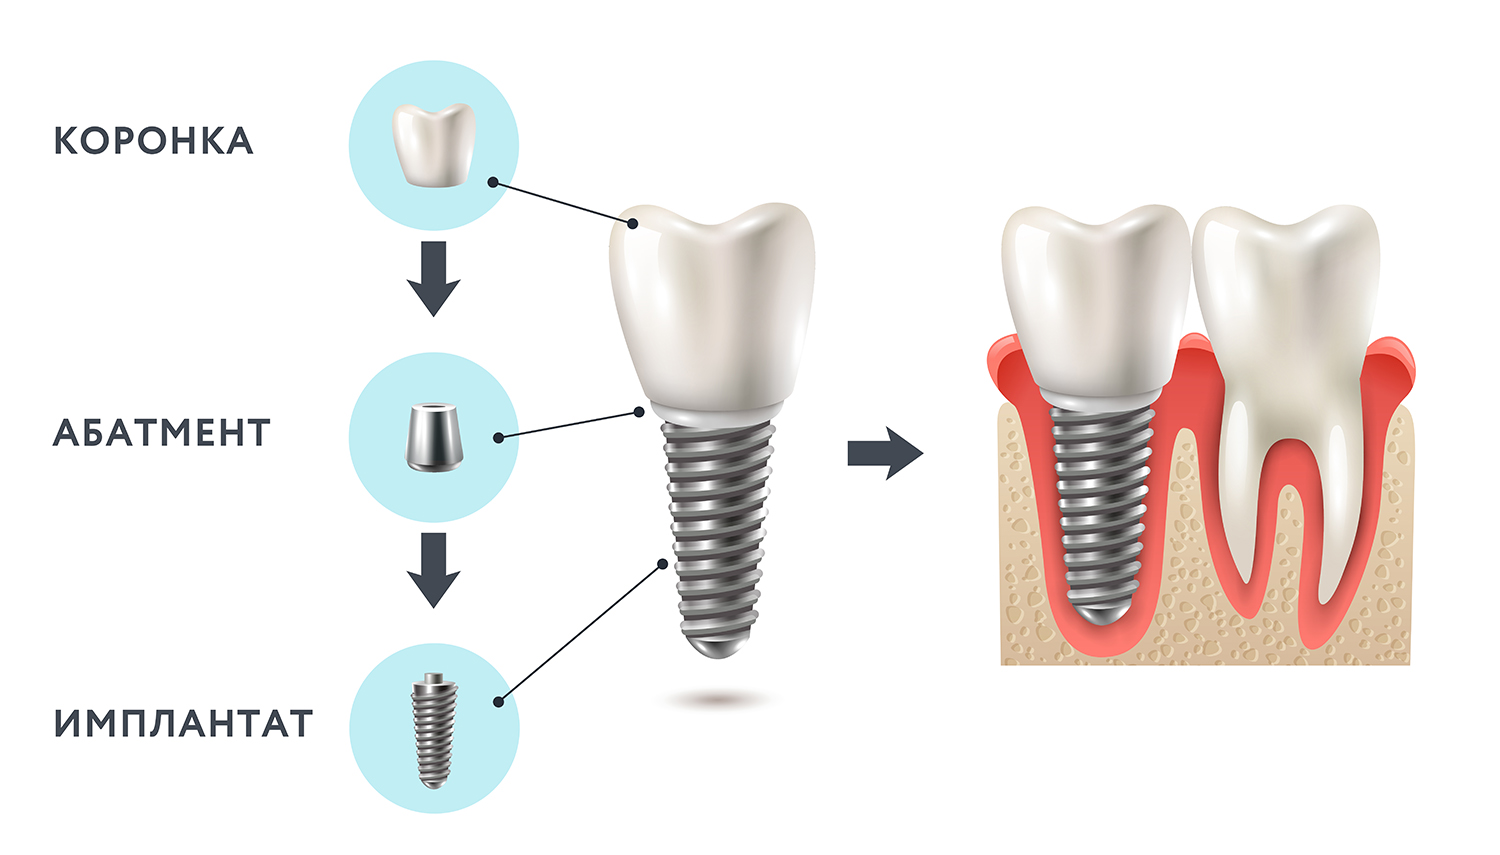

Современные методы протезирования зубов: Рекомендации и советы